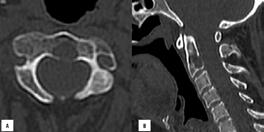

Ryc. 4.2. WBLDCT – ognisko osteolizy w zębie obrotnika.

A – przekrój poprzeczny, B – rekonstrukcja strzałkowa.

W 2018 roku IMWG wydało praktyczne rekomendacje dotyczące akwizycji danych, interpretacji i raportowania WBLDCT u pacjentów ze szpiczakiem plazmocytowym i innymi dyskrazjami plazmocytowymi.